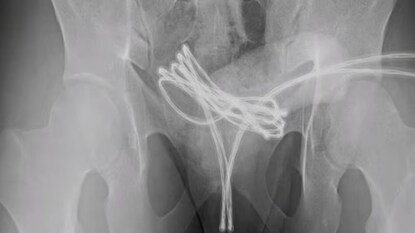

आपत्कालीन शस्त्रक्रियेनंतर तो बरा झाला, पण डॉक्टरांनी इशारा दिला आहे की, असे करणे जीवघेणे ठरू शकते. नुकताच, या प्रकरणाशी संबंधित एक अभ्यास 2020 मध्ये अमेरिकेत प्रकाशित झालेल्या एका मासिकात प्रसिद्ध झाला. नाव न सांगितलेल्या 21 वर्षीय मुलाने 'साउंडिंग' नावाचा प्रयोग केला होता. ही अशी कृती आहे ज्यात लोक गुप्तांगाच्या मूत्रमार्गात (लघवीची नळी) पातळ वस्तू टाकतात. मुलाने यूएसबी केबलला 'यू' आकाराचे वाकवून, दोन्ही टोके बाहेर ठेवून मूत्रमार्गात टाकले. पण यावेळी केबल इतकी आत गेली की तो ती काढू शकला नाही. घाबरून तो रुग्णालयात पोहोचला.

अखेर डाॅक्टरांनी बाहेर काढली केबल

जेव्हा डॉक्टरांनी तपासणी केली, तेव्हा आढळले की केबल मूत्राशयात पोहोचली होती आणि तिथेच अडकली होती. 'क्युरियस' जर्नलमध्ये प्रकाशित झालेल्या अहवालानुसार, डॉक्टरांनी आधी हाताने केबल काढण्याचा प्रयत्न केला, पण ते यशस्वी झाले नाहीत. शेवटी, मुलाला बेशुद्ध करून विशेष उपकरणांच्या मदतीने केबल काढण्यात आली. डॉक्टरांनी हळू हळू केबल बाहेर ओढली, नंतर ती कात्रीने कापली आणि दोन्ही भाग सहज बाहेर काढले.